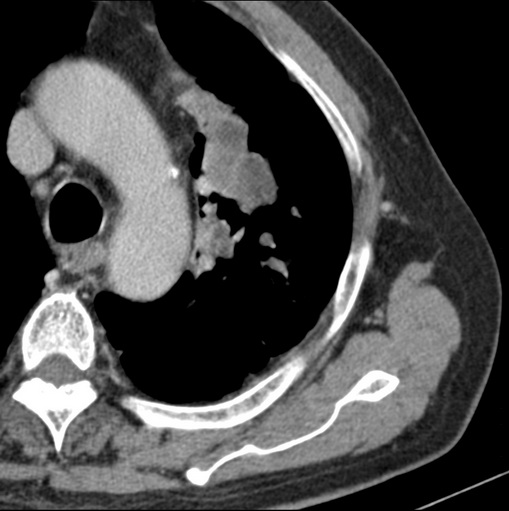

男性患者 81岁 咳嗽 咳痰 咯血

有强化 考虑肺癌肺门淋巴结转移

左肺中心型肺癌并:1.左肺阻塞性肺炎;2.纵隔淋巴结肿大;

强化较典型,左上肺癌并纵膈淋巴结转移;左上肺结核并空洞形成;胸膜增厚.

考虑左上肺癌并阻塞性肺炎,左肺转移、左肺门及纵隔淋巴结转移。

支持左侧中央型肺癌伴肺门及纵膈淋巴结转移。

肿块贴近左肺门,包绕左上肺动脉,形态不规则。肿块增强扫描中度强化。纵膈内主动脉弓左旁间隙、气管隆突前、下间隙见多枚淋巴结影。综上考虑左侧中央型肺癌可能性大。图片没有完整上传,尤其是左肺上叶支气管分支层面没有上传,因此不好判断是叶支气管中断还是段支气管中断。另外,下图红色部分所示是“黏液支气管征”吗?